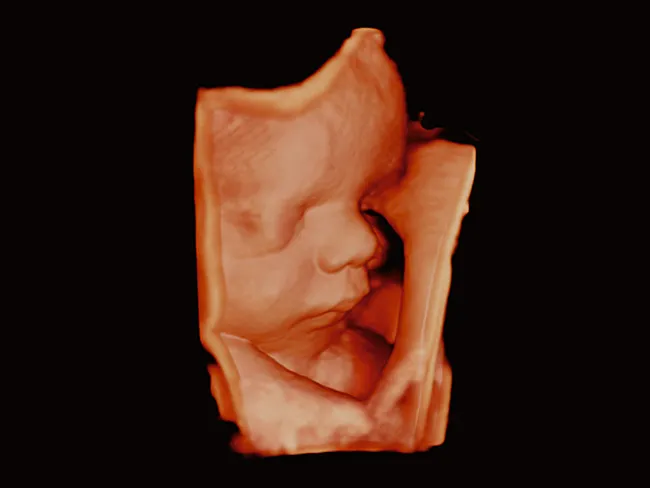

Luminance обеспечивает естественную 3D-визуализацию высокого качества и четкости, обеспечивая четкую визуальную обратную связь по глубине и детализации начиная с первого триместра беременности.

Как занятый врач, так и пациент могут воспользоваться 2D-визуализацией высокого разрешения и объемным ультразвуковым исследованием. Комплексный пакет объемной визуализации Aplio расширяет ваши диагностические возможности и выходит на новый уровень визуализации благодаря исключительному качеству изображения и бескомпромиссному рабочему процессу.